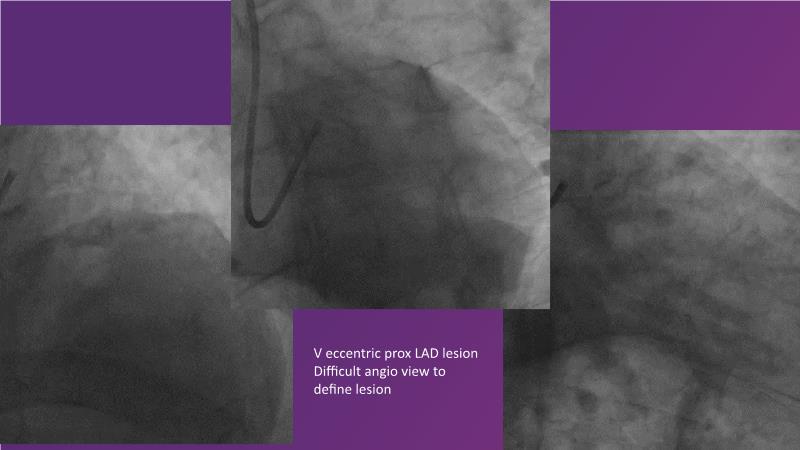

Explore the latest trends in percutaneous coronary intervention (PCI) in this session, focusing on stentless PCI and the role of sustained limus release technology. Join the discussion on how sustained limus release can expand the indications for drug-eluting balloons (DEB) and minimize the use of metal stents, gain insights into the importance of vessel preparation and learn which tools to utilize in specific scenarios.

- To review clinical scenarios when a stent is not required